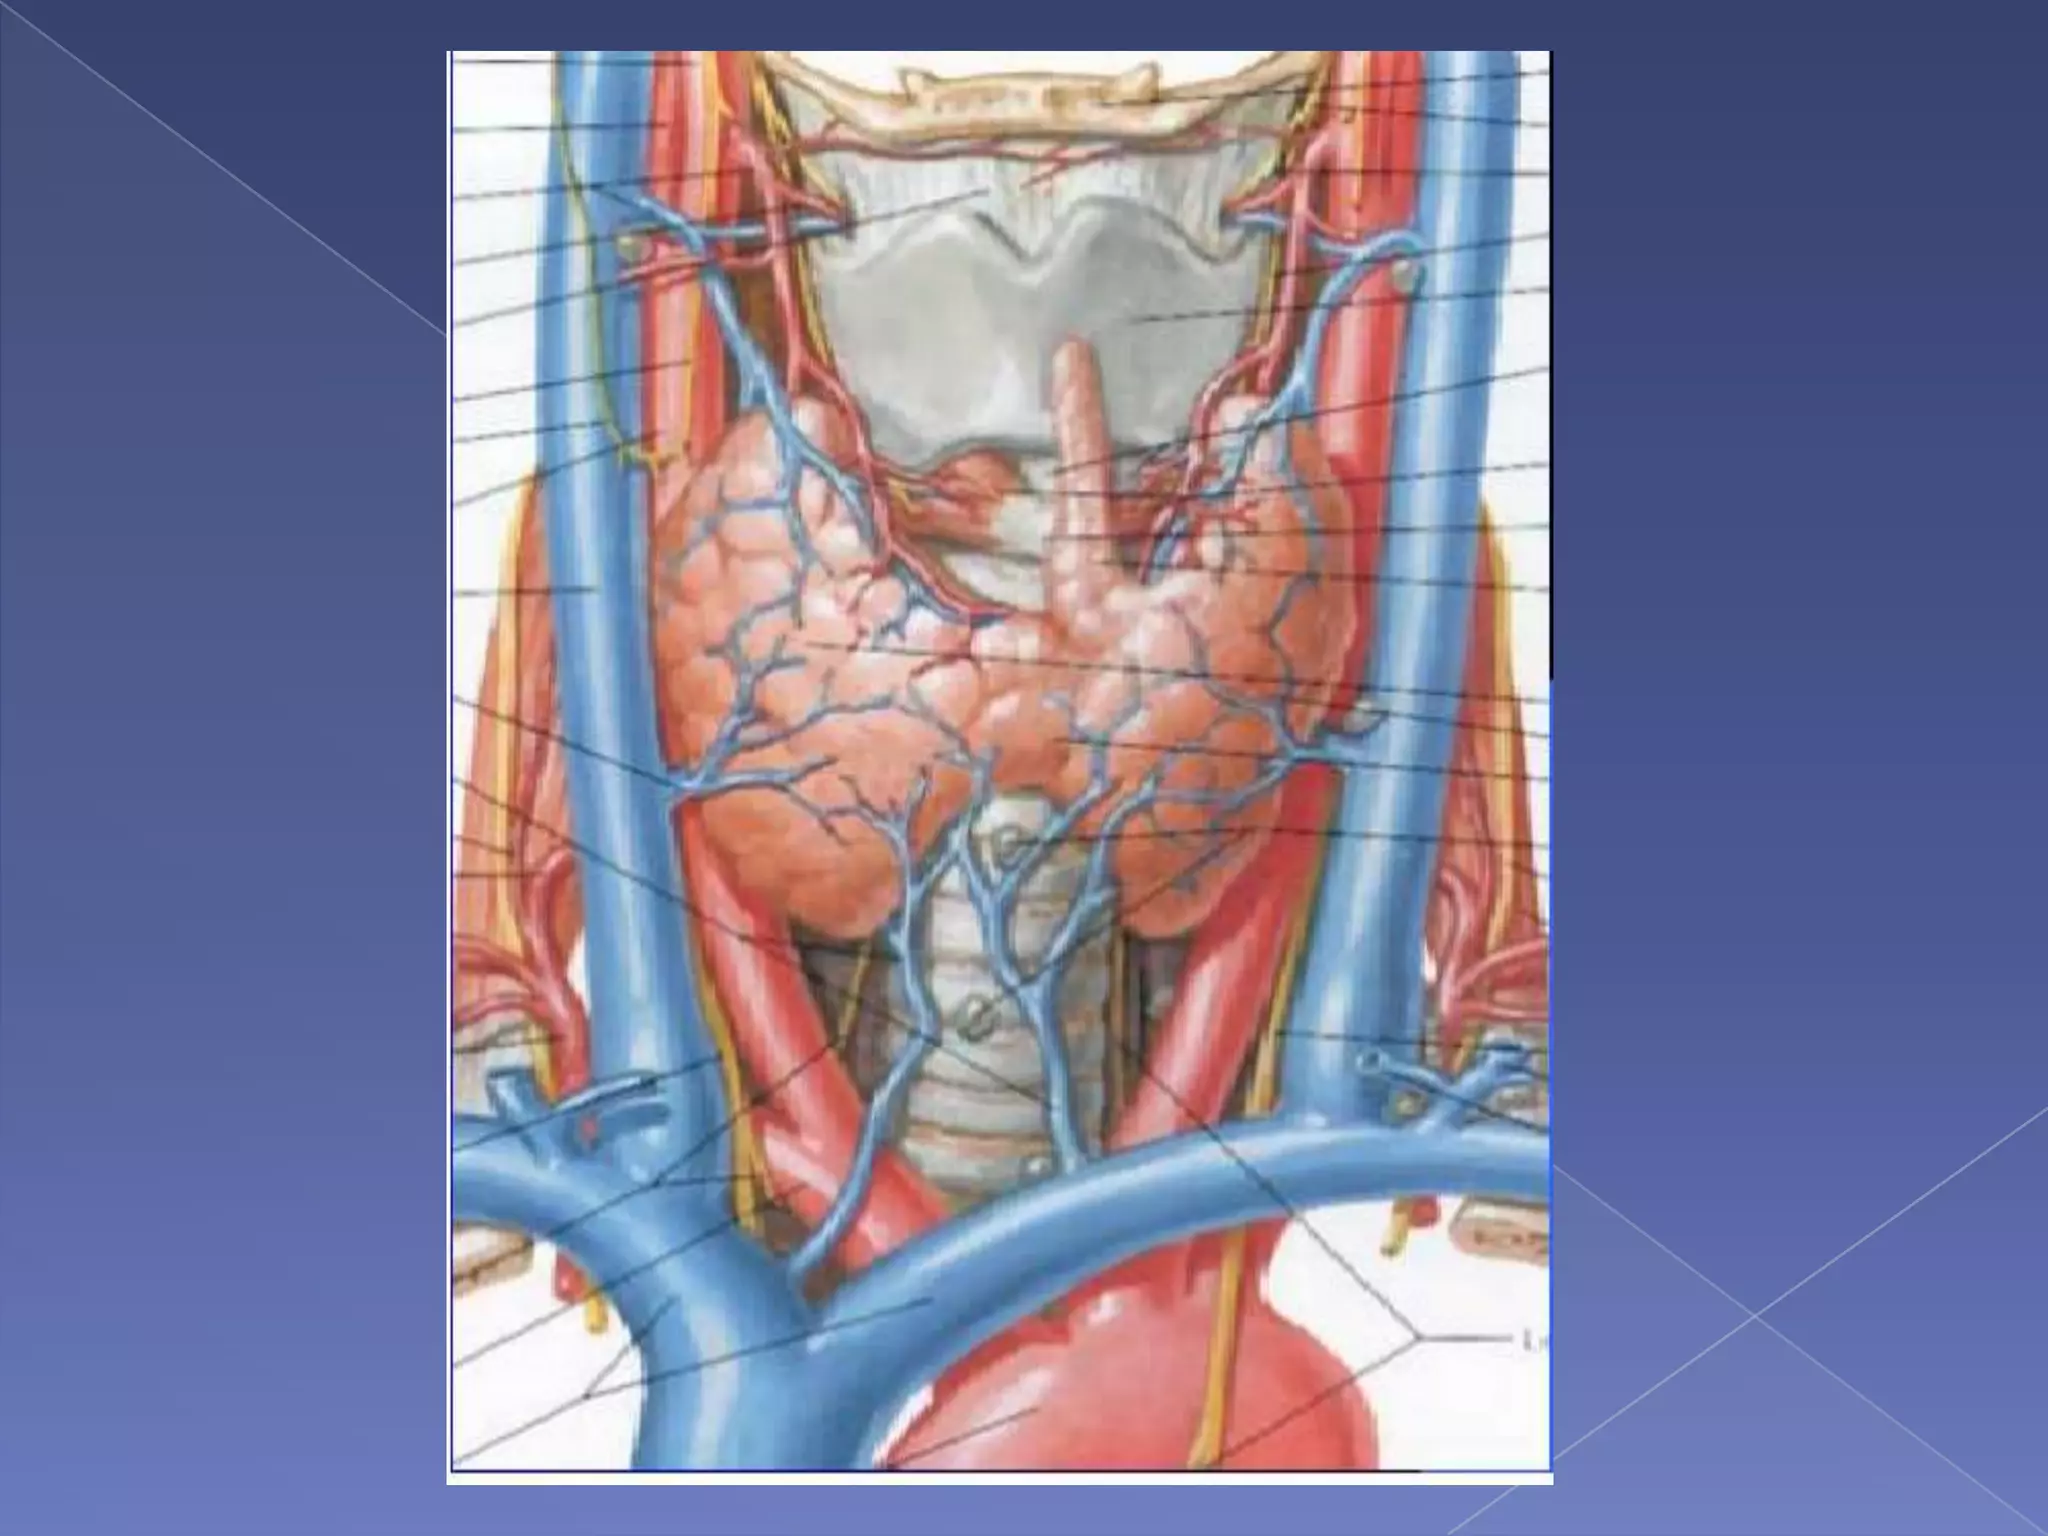

AnatomyLocate deep to the sternohyoid muscle, from level C5 to T1 vertebrae or anterior to the 2nd and 3rd tracheal rings.Thyroid gland is attached to the trachea by the lateral suspensory (Berry) ligaments.

Blood supplyBlood supply: sup. & inf. thyroid arteriesthyroid ima artery (1.5% to 12%)

Lymph vessels: drain to prelaryngeal,

pretracheal

paratrachealnodes.

Innervation:

superior,

middle,

inferior sympathetic gangliaVenous drainage Superior thyroid v  (to IJV)middle thyroid v.  (to IJV)Inferior thyroid v. (to brachiocephalic trunk)